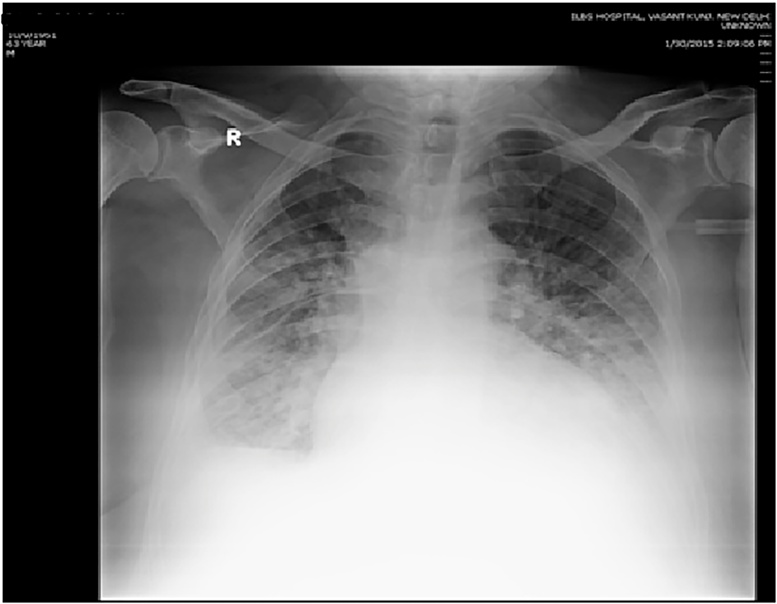

Figure 3.

Atypical imaging – new onset pleural effusion noted in addition to areas of reticular and ground-glass opacities in the lung parenchyma.